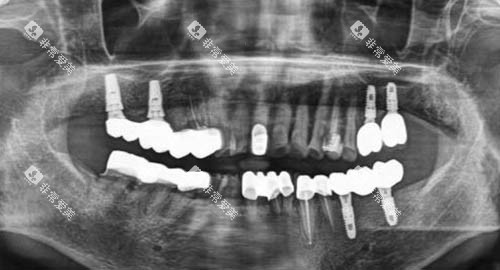

种植牙

烤瓷/全瓷牙